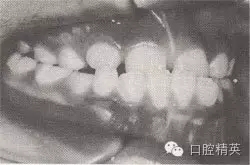

患者,女,10歲,替牙頜。磨牙近中關(guān)系。前牙反頜,下頜前突。下頜體稍長,下頜位置前移,上頜前頜骨區(qū)發(fā)育稍差。

診斷:安氏Ⅲ類前牙反猞,骨性Ⅲ類,毛氏Ⅱ¹。

矯治設(shè)計:面罩前牽引上頜,移下頜位置向后,抑制下頜生長??趦?nèi):全牙弓夾板,后牙平面頜墊式活動矯治器。矢狀關(guān)系調(diào)整后,去掉前牙區(qū)夾板,雙曲舌簧加力移切牙向唇向。

治療時間:2個月,上頜前移,下頜位置后移,切牙覆猞、覆蓋正常。

圖8-44 安氏Ⅲ類錯頜,混合牙列前牙反頜矯治前后面頜像

矯治前面相

矯治后面相